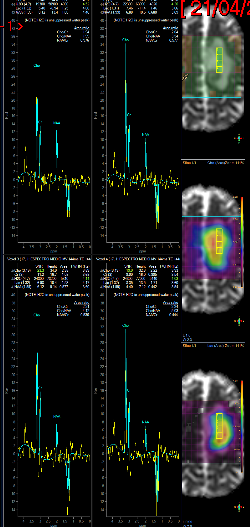

Fig3a,b – Espectroscopia de Múltiplos Voxels (EMV) em caso de glioma de alto grau (Astrocitoma anaplásico – III) frontal esquerdo. Traçados de mini voxels colocados no interior e no tecido cerebral vizinho (a, b), para avaliar grau de invasividade tumoral mostram níveis elevados de cholina dentro e fora da lesão.

Fig3c,d – Espectroscopia de Múltiplos Voxels (EMV) em caso de glioma de alto grau (Astrocitoma anaplásico – III) frontal para sagital esquerdo. Traçados de mini voxels colocados no interior e no tecido cerebral vizinho para avaliar grau de invasividade tumoral mostram níveis elevados de cholina dentro e fora da lesão redução do NAA (c) e acúmulo de lactato(d).

A figura acima apresenta mapa de metabólitos (cholina e NAA) que mostram redução de NAA por substituição de tecido normal por células neoplásicas e acúmulo de cholina por proliferação celular glial (c). Também o mapa de metabólitos (cholina e lactato), mostra, além de acúmulo de cholina, a presença de lactato, inferindo hipóxia intratumoral (d).